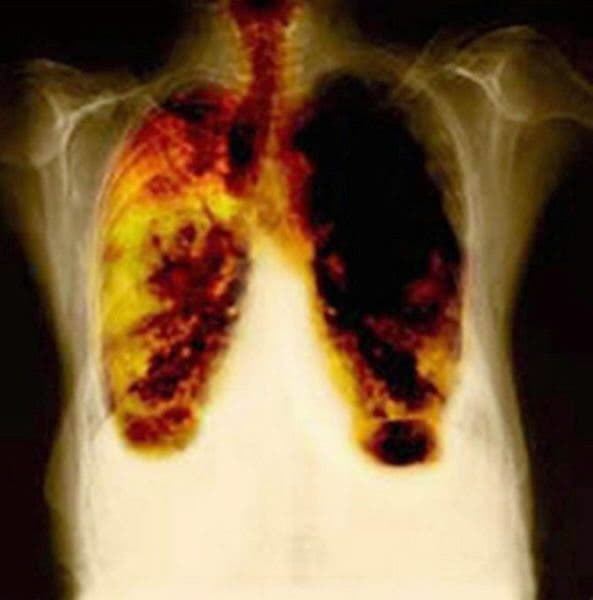

Del 100% de los tumores pulmonares que se diagnostican sólo el 25% se pueden operar; 1 de cada 4 porque son grandes o afectan a estructuras dentro del torax que la cirugía no puede extirpar.

Del 25 % que se opera sólo el 25 por ciento vive más de cinco años. La supervivencia global del carcinoma broncogémico está en torno al 10-12% de los pacientes que se diagnostican.